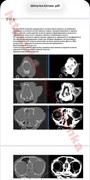

Сдали ей все инфекции - отрицательно. На рентгене полностью забита 1 ноздря. Отправили на передержку с лечением, но Шипучке стало только хуже. Сейчас она находится в стационаре. Было сделано КТ, у кошечки уже разъело левую часть лицевой кости, подозрение на онкологию...

Сейчас нужно дать малышке передержку с медицинским уходом, оплатить долг за стационар и уколы, а так же собрать средства на риноскопию, чтобы взять биопсию на гистологию, к сожалению без неё онкологию нельзя исключить